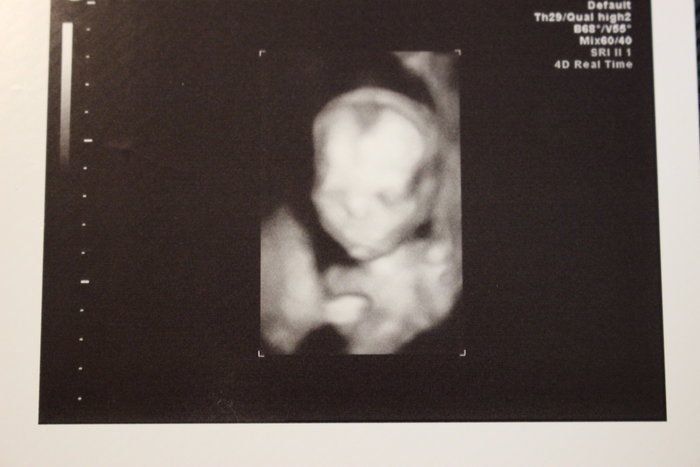

チャーミー小結さんの妊娠18週目のエコー写真

4D画像になり目鼻立ちもはっきりと確認できます。赤ちゃんの胎動は”金魚を手のひらで包み込んでいる感じ”がしました。赤ちゃんの心臓に異常がないかを確認し、母体側では子宮筋腫が胎盤裏に位置しているので注意が必要だと説明されました。信頼のおける医師と出会い、その医師に全てを託す思いで分娩申込書を提出しました。